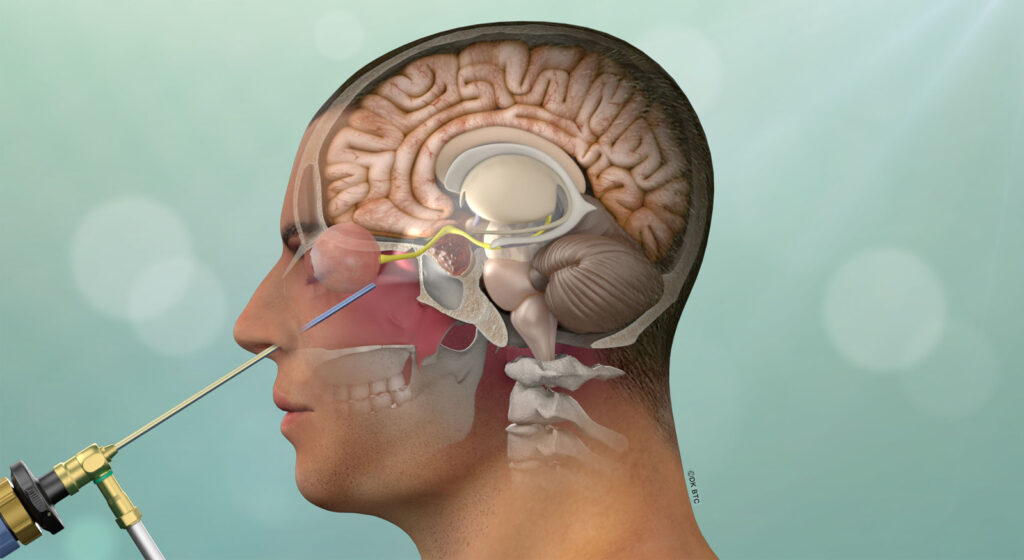

While often described as a “rare” disorder, “relatively uncommon” may be a more apt descriptor of Cushing’s disease. It is much more common in women than men and while it can develop at any age, it tends to manifest between ages 25 to 55 years. The good news is that once Cushing’s disease is diagnosed, endonasal tumor removal performed by experienced pituitary surgeons has a very high success rate and safety record. Overall, 75-80% of patients achieve remission with surgery, and the resultant normalized cortisol levels lead to resolution of many of the associated problems of Cushing disease. If surgery is not initially successful, repeat endonasal surgery, use of medications, focused radiation (radiosurgery) and/or removal of the adrenal glands (bilateral adrenalectomy) can lead to remission in the vast majority of patients. These therapies need to be carefully considered, ideally in a multidisciplinary setting with a team of pituitary specialists.

After diagnostic confirmation of Cushing’s disease has been made, endonasal removal of the adenoma and preservation of the normal pituitary gland is the treatment of choice. When performed by an experienced pituitary surgery team, long-term remission rates average close to 80% and the risk of major surgical complications is very low, including a risk of new pituitary gland failure of less than 5%. The success rates are highest (typically over 90%) in patients with a clearly defined non-invasive microadenoma (less than 1 cm in diameter) as seen on MRI. For patients with invasive adenomas or those in which the adenoma is not visible on high-quality pituitary MRI with dynamic sequencing, remission rates are substantially lower (typically ranging from 40-70%).

The Pacific Pituitary Disorders Center has a long experience and academic track record in treating patients with pituitary adenomas and Cushing’s disease (CD) in particular. We also treat many patients with recurrent Cushing’s disease. For the last 14 years we have used an exclusively endoscopic endonasal approach given the optimal visualization of the pituitary gland and related skull base anatomy afforded by the hi-definition endoscope. For every case we utilize high-definition cameras and monitors, surgical navigation and Doppler probe for real-time carotid artery localization to maximize effectiveness and safety of the surgery. Our typical pituitary adenoma surgery takes about 3-4 hours and most patients are discharged home a day after surgery.